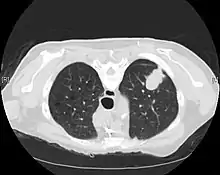

Imaging

A chest x-ray (radiograph) is often the first imaging test performed when a person presents with cough or chest pain, particularly in the primary care setting. A chest radiograph may detect a lung nodule/mass that is suggestive of cancer, although sensitivity and specificity are limited.

CT imaging provides better evaluation of the lungs, with higher sensitivity and specificity for lung cancer compared to chest radiograph (although still significant false positive rate[25]). Computed tomography (CT) that is specifically aimed at evaluating lung cancer includes the chest and the upper abdomen. This allows for evaluation of other relevant anatomic structures such as nearby lymph nodes, adrenal glands, liver, and bones which may show evidence of metastatic spread of disease.[4] Indeed, the US Preventative Services Task Force recommends annual screening with low-dose CT in adults aged 55 to 80 years who have a 30 pack-year smoking history and currently smoke or have quit within the past 15 years, with certain caveats (see Lung cancer screening).[26]

Nuclear medicine imaging, such as PET/CT and bone scan, may also be helpful to diagnose and detect metastatic disease elsewhere in the body.[7] PET/CT uses a metabolically active tracer that allows clinicians to identify areas of the body that are hypermetabolic. Increased uptake of the tracer occurs in malignant cells and areas of inflammation or infection. Integrating the imaging reflective of metabolic activity with normal CT imaging allows for higher sensitivity and specificity compared to PET alone.[4]

MRI is reserved for patients with advanced disease where intracranial, or brain, involvement is likely. It is also helpful for evaluating the extent of chest wall, diaphragmatic, brachial plexus (such as in the case of superior sulcus tumors), or spine involvement.[4]